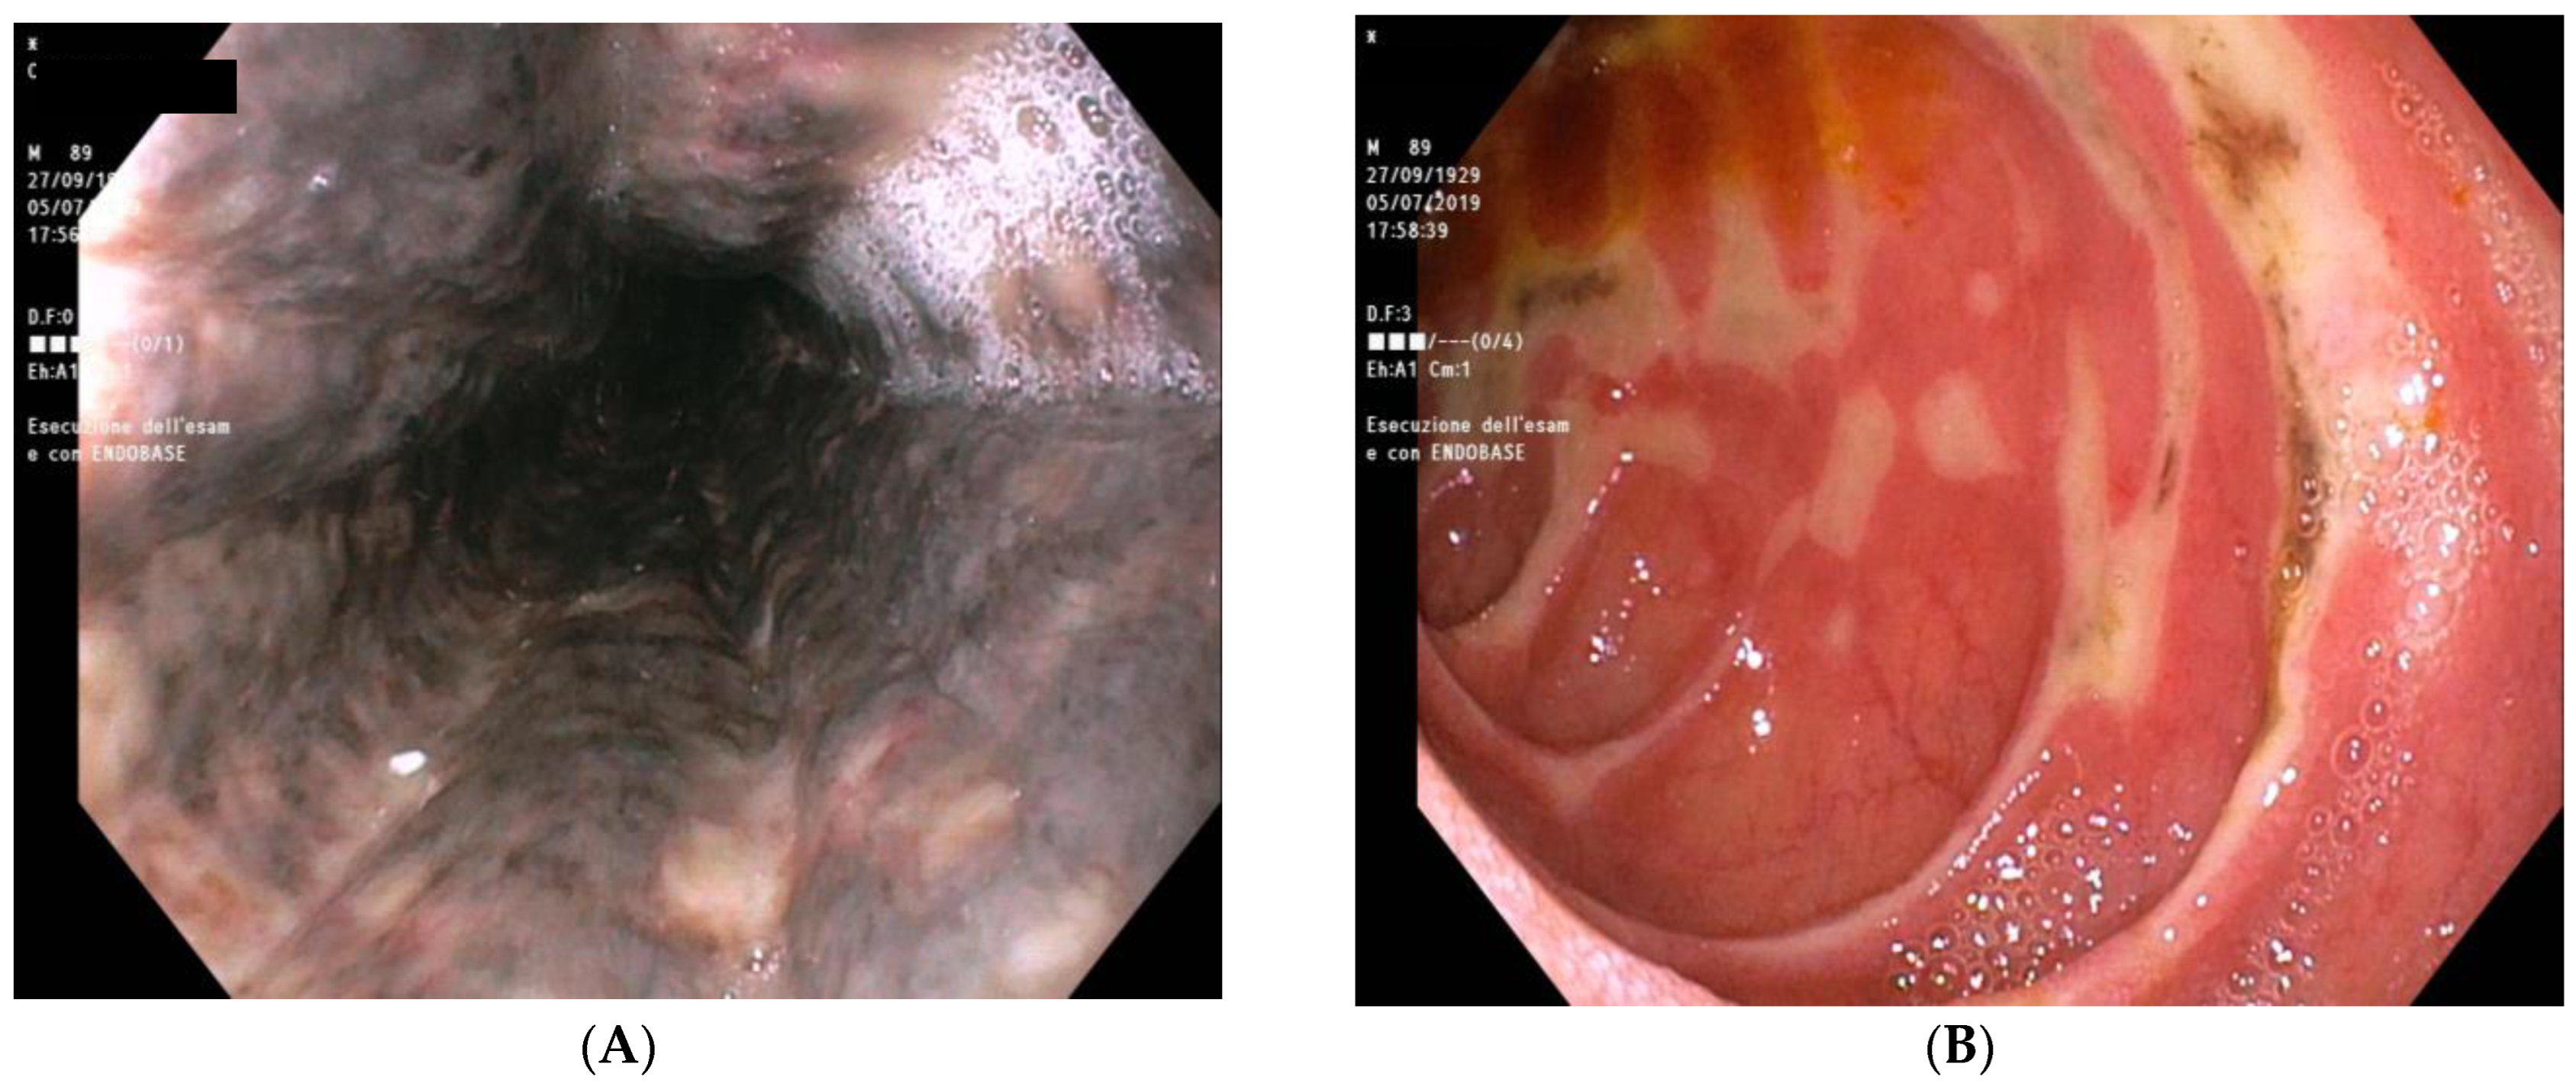

2.8. Further Diagnostic Work-Up